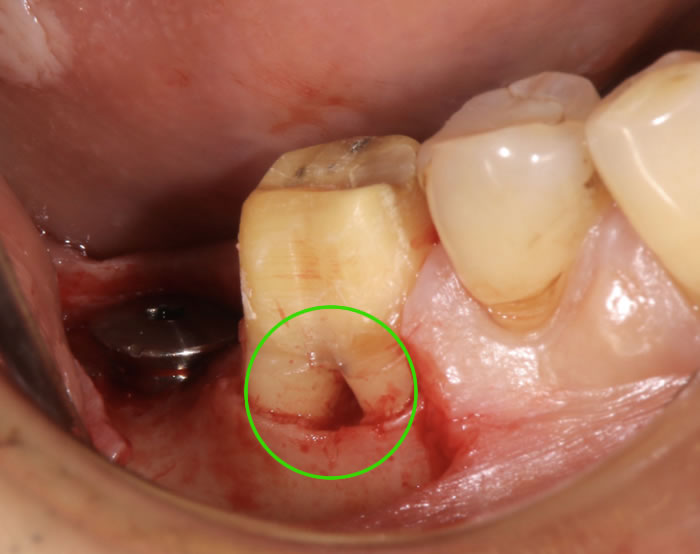

後ろの歯のないところには骨吸収が進んでいたのでショートインプラント(短い)を用いて低侵襲なオペで機能回復させます。

長さ4ミリのインプラントも適切な治療で永続性を手に入れることができます。